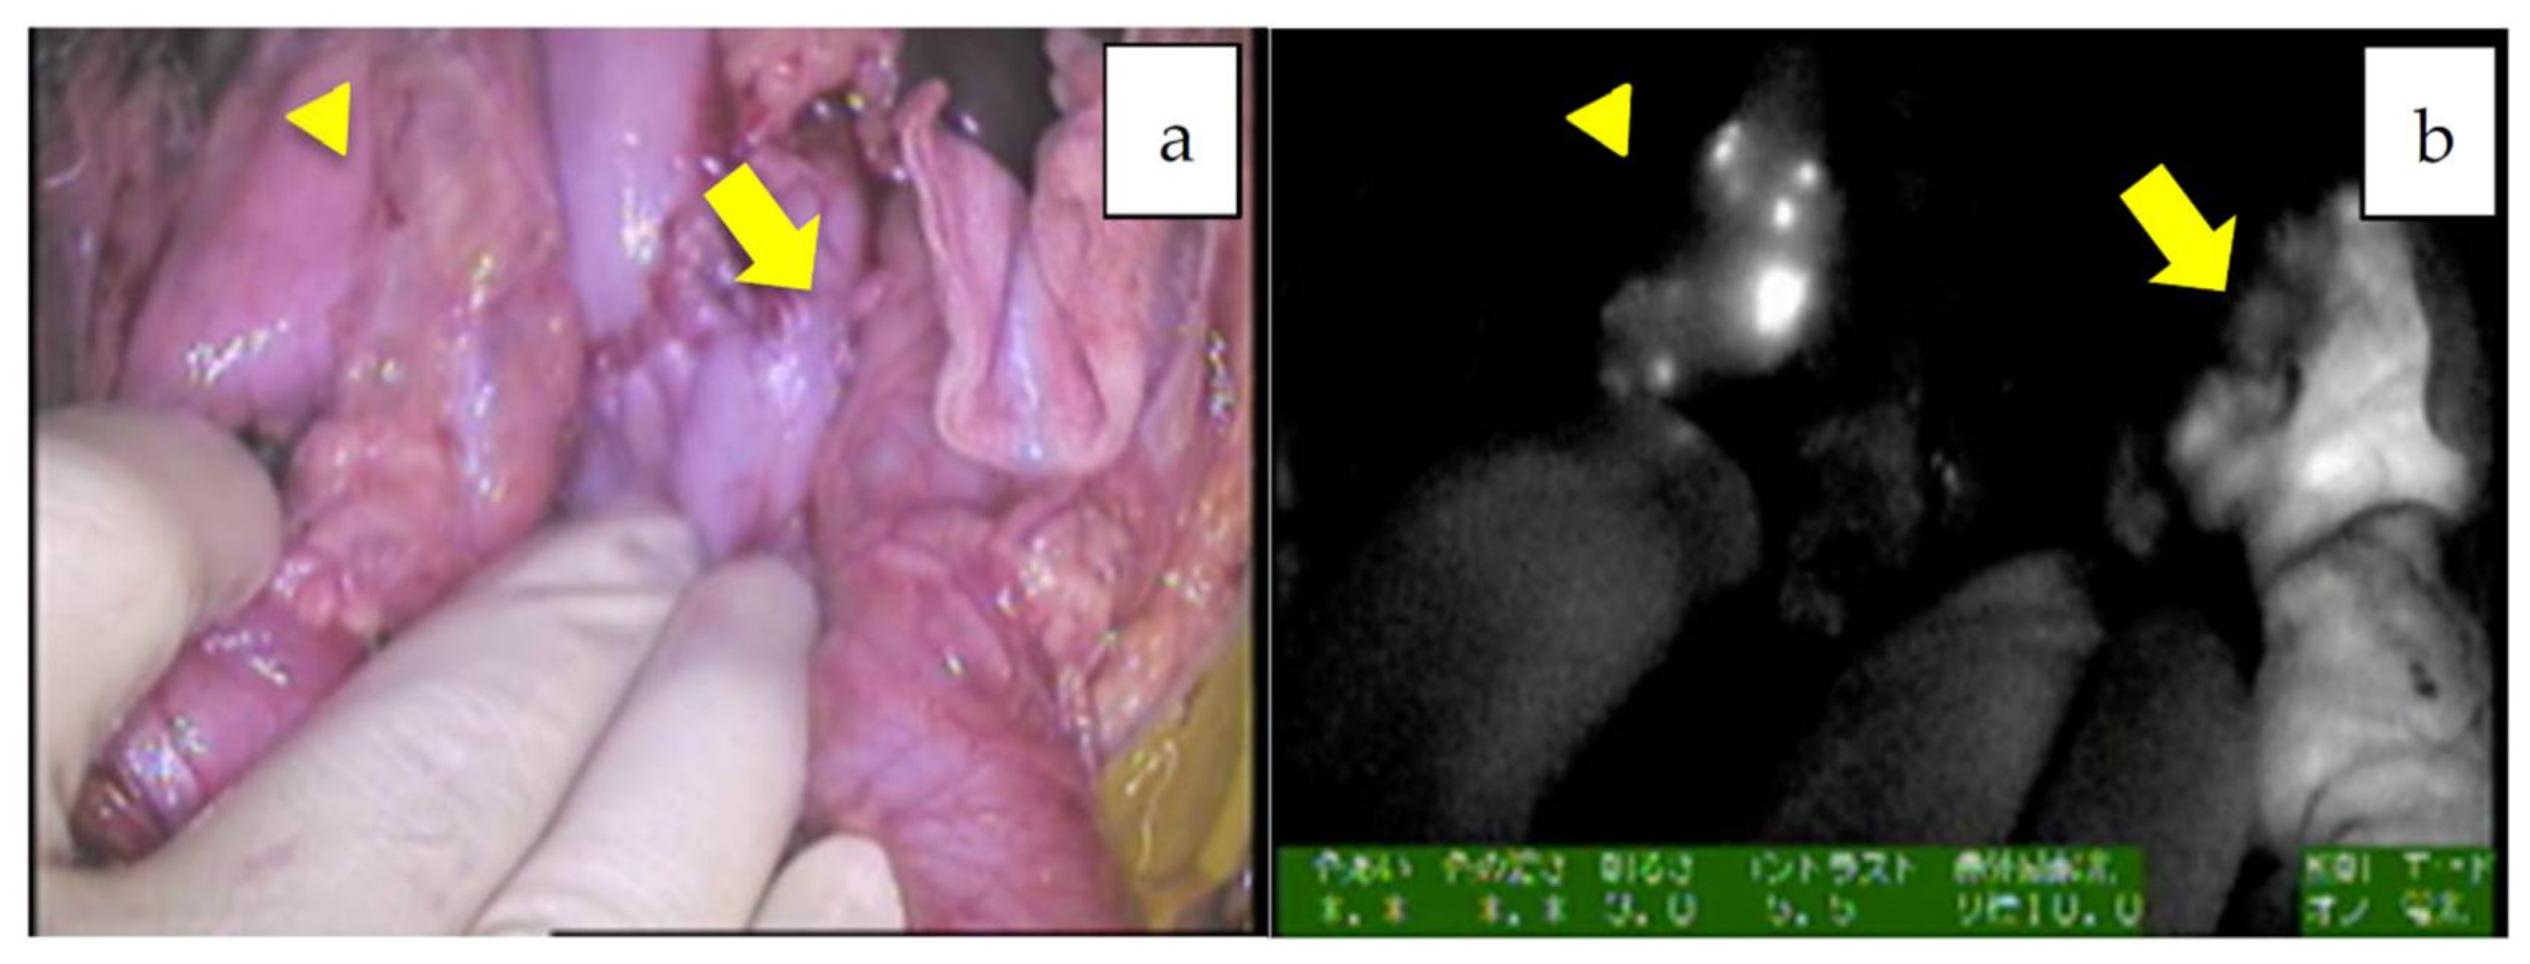

When metastatic HBs in the abdominal cavity are targeted, such as in cases of disseminated nodules or lymph nodes, the fluorescence excreted into the bowels may interfere with the NIR view. In such situations, ICG should be given around 72–96 h prior to the operation in order to minimize nonspecific fluorescence. For example, ICG was administered 72 h before resection for peritoneal dissemination in patient 8, as shown in Figure 6a–d [44], and for metastases to the pleura and diaphragm in patient 20, as shown in Figure 7a–c [33]. In these cases, fluorescence-guided surgery greatly helped surgeons identify the exact location and extent of the tumor even in a dense, adhesive operative field. The uptake of ICG in metastatic HBs or HCCs is presumed to be mediated by the same transporters as the primary tumors. In contrast, peritoneal metastases from colorectal cancer can be visualized by ICG through the enhanced permeability effect, which is the passage of ICG through abnormal permeable tumoral vessels [46].

Figure 6.

Peritoneal metastases in the patient 8, which were successfully removed with the help of NIR mode. Normal white light mode viewing the abdominal cavity (a,c) and NIR mode (b,d).